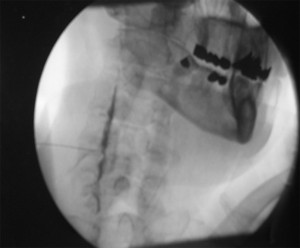

Posición del paciente en decúbito supino con almohada bajo los hombros, se coloca el arco de fluoroscopia en posición para visualizar C6-C7-T1 y se marca el punto de entrada en la piel haciéndolo coincidir en la unión de la apófisis transversa con el cuerpo vertebral de C7, previa separación con el dedo índice de la mano, de la tráquea y el pulso carotideo. Se le pide al paciente que respire por la boca y se introduce la aguja un poco medial y craneal para evitar el vértice pulmonar y la arteria vertebral. Una vez haga contacto óseo se retira la aguja 2mm  y pasamos el arco de fluoroscopia posición lateral y se debe ver la profundidad de la aguja ventral a una línea imaginaria que pasa ventral a los forámenes intervertebrales. Inyectar 0.5ml de contraste para asegurarnos la posición correcta.